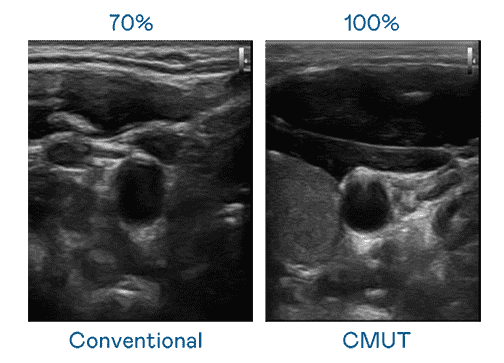

CMUT 技术是一种用电容式微机电元件来产生超音波讯号的技术。。。。与传统 PZT 压电式技术相比,,,CMUT 频宽增加 30%,,,更宽频的超音波讯号让影像解析度大幅提升,,是实现高影像品质医疗超音波扫描、、、、促进精准医疗发展的关键技术。。。

大频宽带来超清晰影像

超音波影像的解析度高低,,,首先取决于探头能发出的讯号频宽。。。。万利 CMUT 可提供高清晰的超音波讯号,,提供高频宽、、、高灵敏度、、影像纹理细节更高的超音波影像,,,协助医护人员缩短影像判读时间及利用精准的医疗影像进行诊断。。。